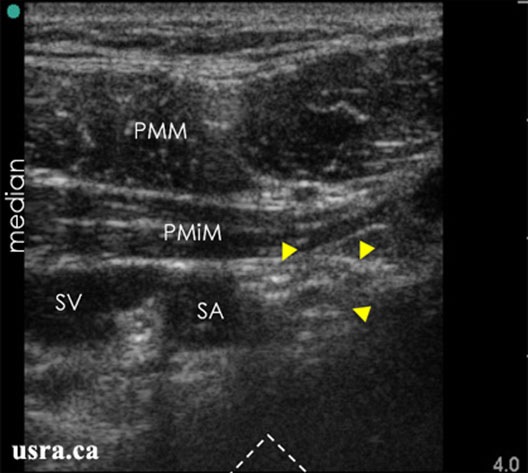

The stimulating needle is inserted immediately next to the ultrasound probe at approximately 60–70° angle. An in-plane approach is recommended for continuous direct visualization of the needle under ultrasound (Figure 7). Injection of local anesthetic lateral to the subclavian artery and especially close to the posterior cord, with a U shape spread of the injectate is most often associated with a reliable block (Figure 8). A dual technique, using PNS in conjunction with US may be used if needed.

Figure 8. Sonoanatomy of the infraclavicular region with the transducer placed transverse below the clavicle; arrowheads = nerves; PMM & PMiM = pectoralis major & minor muscles; SA & SV = subclavian artery & vein.

From usra.ca website, with permission.